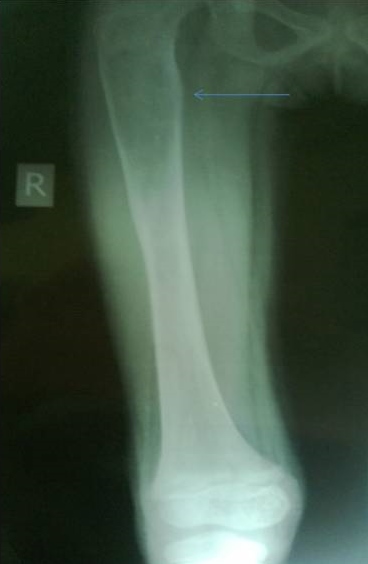

X-ray of the lower limbs showed fibrous dysplasia involving the left femur [Figure 2] and skull x-ray showed ground glass appearance of the left orbit. [Figure 3]

Click here to download Figure 2Figure 2.Well defined geographic lesions showing ground glass haze and sclerotic margins is seen involving left femoral metaphysics and diaphysis.